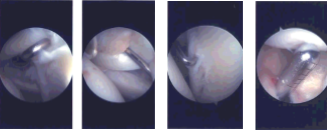

Intraoperative Arthroscopy Images

An anterosuperior entry portal was made with the use of spinal needle and cannula was Inserted. Examination of the joint showed fraying of the anterior margin of the glenoid as well as the glenoid labrum. There was minor fraying of the labrum at the attachment of the biceps also.

Examination of biceps showed no tenosynovitis or tears. Examination of the intra articular portion of the rotator cuff showed no tears. There was grade I, grade II osteochondral lesion of the posterior part of the head of humerus.

Shaver was inserted and debridement of the labrum as well as the glenoid and humeral head were performed. The arthroscope was entered from the anterior portal and the shaver entered from the posterior portal to complete the debridement.

Examination of the rotator cuff showed tear at the posterior margin of the supraspinatus with interstitial tearing intratendinous. Also shown was acromial spur and AC arthritis impinging on the rotator cuff. Acromioplasty was performed with the use of a thermal wand followed by 6.0 shaver.

Distal clavicular excision was also performed with the use of a thermal wand followed by burr. About 1 cm of distal clavicle was excised. Decision was made to repair the rotator cuff tear with the bioinductive implant from Smith & Nephew.

The bioinductive implant was inserted through the lateral portal into the joint. Superior portal was made for the insertion of tacks. The tacks were inserted through the superior portal and the bioinductive implant was tacked onto the rotator cuff with the use of PLA tacks x7. Finding it in satisfactory position and fixation, final pictures were taken and saved.